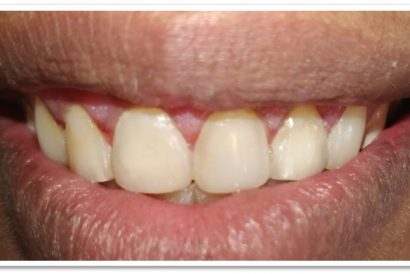

Before

Patient Name: Poonam Joshi

Tooth Involved : 21

Diagnosis : Hypoplastic Stains With 21

Treatment : Direct Composite Using Nanohybrid Composite

Stains Masked Using IVOCLAR EMPRESS COLOUR White And Honey

After